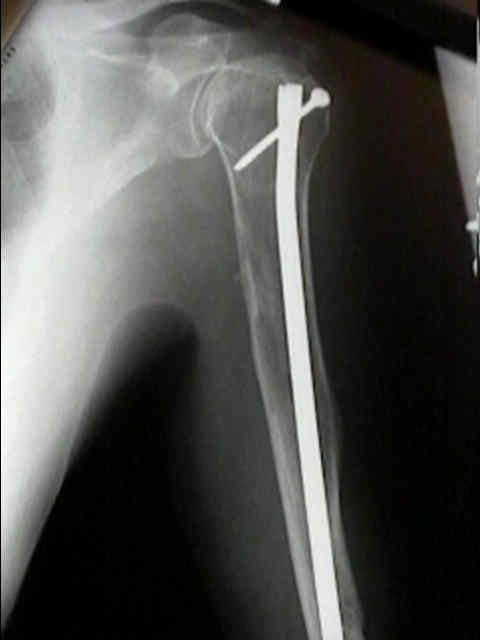

Se localiza, preferentemente, en los huesos donde existe médula ósea roja: vértebras, costillas, esternón, pelvis, cráneo y huesos largos (tercio proximal fémur y húmero).

Las fracturas patológicas de columna o fémur pueden ser el primer

síntoma. Se producen con un traumatismo mínimo o incluso sin trauma.

Fracturas patológicas

Radiográficos:

Las radiografías normales pueden mostrar osteopenia difusa.

"Lesiones perforadas" o en "sacabocado" sin ninguna formación de nuevo-hueso circundante. Su diámetro es variable (hasta 5 cm.), redondas y múltiples.

Con el tiempo las lesiones pueden cambiar de osteopenia difusa a más permeativa con patrón destructivo apolillado, y a veces con expansión cortical.

La destrucción del hueso ocurre con poca o ninguna formación de hueso reactivo a menos que haya una fractura patológica.

Los mielomas pueden presentarse como lesión solitaria o más normalmente como un tumor difuso, involucrando múltiples huesos, incluyendo vértebras, cráneo, pelvis y fémures.

Busque una o mas fracturas en la columna.

Radioterapia:

El mieloma es sensible a la radioterapia, y la reosificación de los defectos del tumor pueden ocurrir dentro de varios meses.

La radioterapia se recomienda para el dolor

rebelde del hueso, especialmente si el dolor es localizado.

Puede ser dramáticamente eficaz en el alivio de los síntomas.

Fijación

quirúrgica:

El enclavado IM femoral profiláctico: